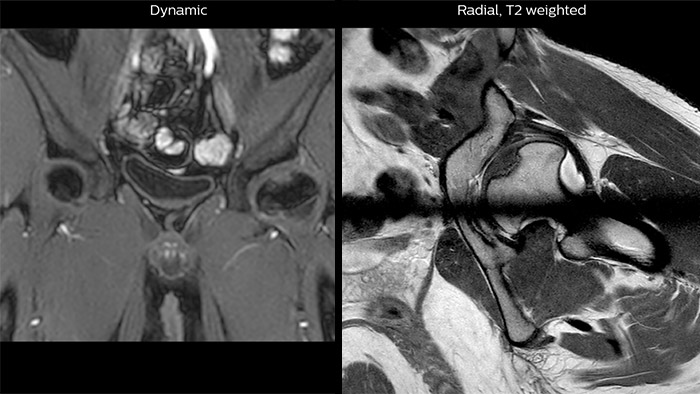

Perthes disease in left hip The affected area on the upper circumference of the left hip shows contrast uptake in the dynamic scan. The radial scan nicely depicts the hip area, despite the dark shape in the center that is inherent to the radial way of scanning.

Features that provide remarkable benefits to Dr. Junge include Compressed SENSE, which allows to elevate spatial resolution, signal and scan time. MultiVane XD and 3D VANE XD employ radial k-space sampling and help to mitigate motion artifacts and improve robustness for different contrasts and for all age groups. The mDIXON FFE and mDIXON TSE methods nicely address challenges in fat-free imaging and provide multiple contrast types from one single scan. The achievable large field of view (FOV), high resolution and flexible echo times are certainly a huge benefit in examining children.